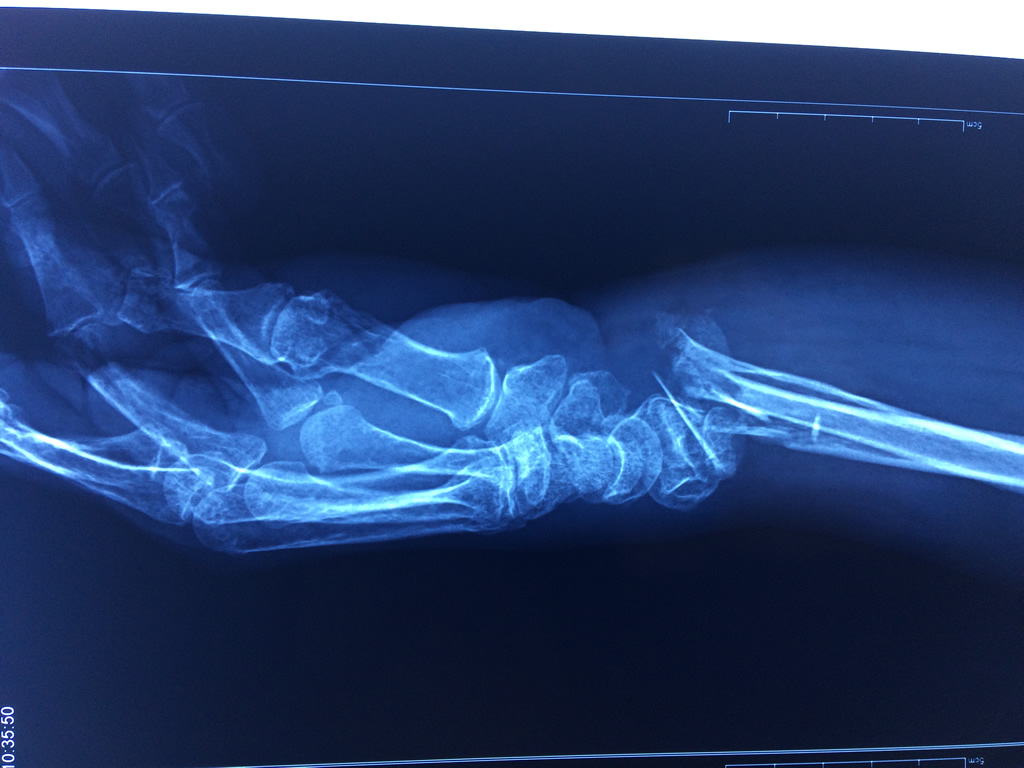

Cirugías de Codos - Cirugías de Muñecas y Manos

Los procedimientos más comunes en cirugía de la mano son aquellos destinados a reparar traumatismos, incluyendo lesiones de tendones, nervios, vasos sanguíneos, y articulaciones; huesos fracturados; y quemaduras, cortes, y otros daños de la piel.